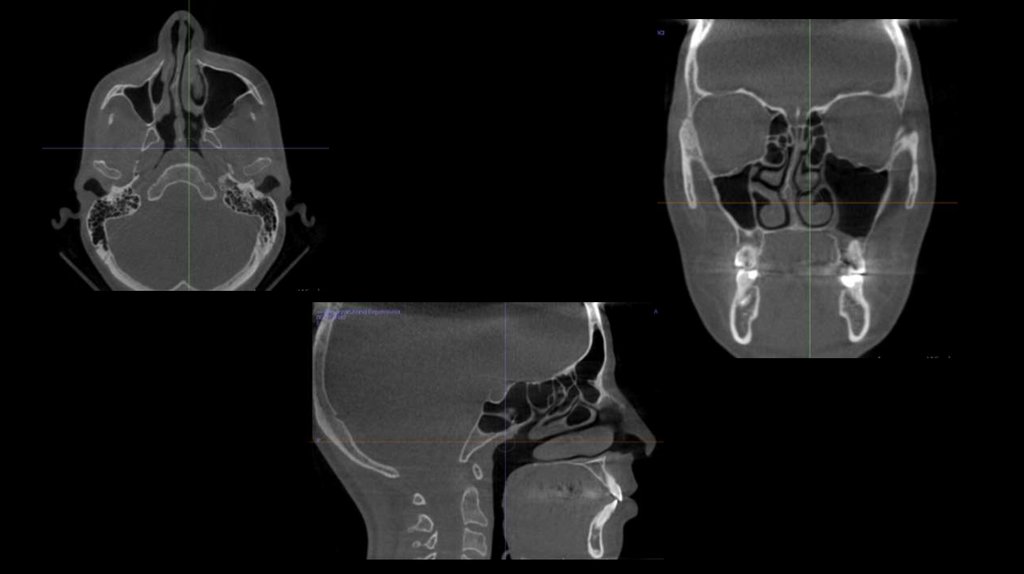

КЛКТ

10.

КТ спереди

11.

КТ справа

КТ слева

12.

КТ ВНЧС

КТ дыхательные пути